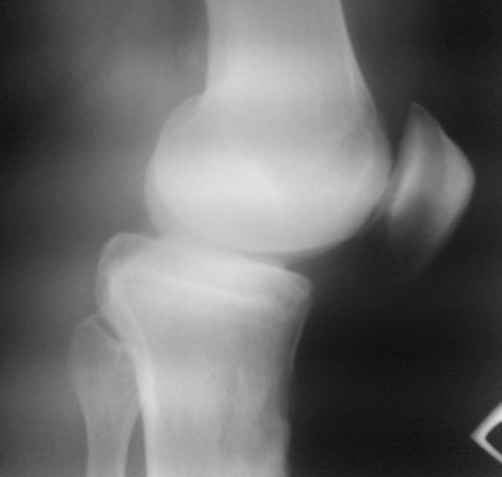

пациент наконец то объявился вновь и мы смогли выполнить новые снимки как лежа так и в нагрузке

если у вас остались силы, давайте обсудим